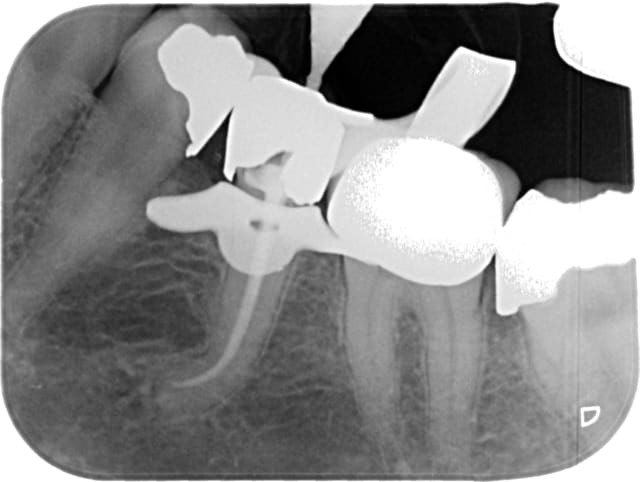

pour déterrer ce post je vous mets un zoli sapin de noël en avance

par provoc on s'est amusé à faire une photo

pour répondre à la question avec quoi j'obture : maitre cone et condensation verticale simplement

cadeau (si je puis me permettre) de fin

mon objectif avait été de dire qu'on pouvait aussi faire simple mais la critique SYSTEMATIQUE me casse les c...